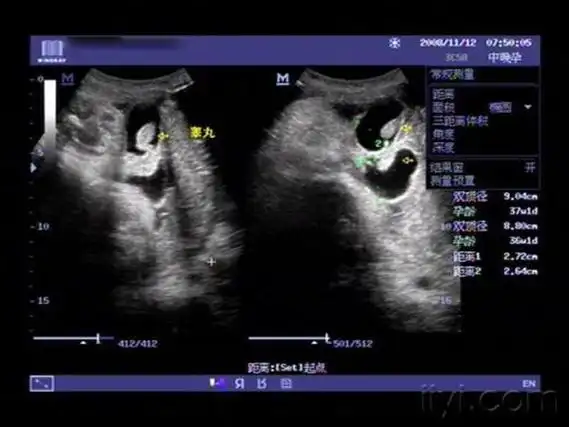

孕26周四维下睾丸的样子 如何看四维彩超识性别

谁手里有四维彩超胎儿睾丸图片